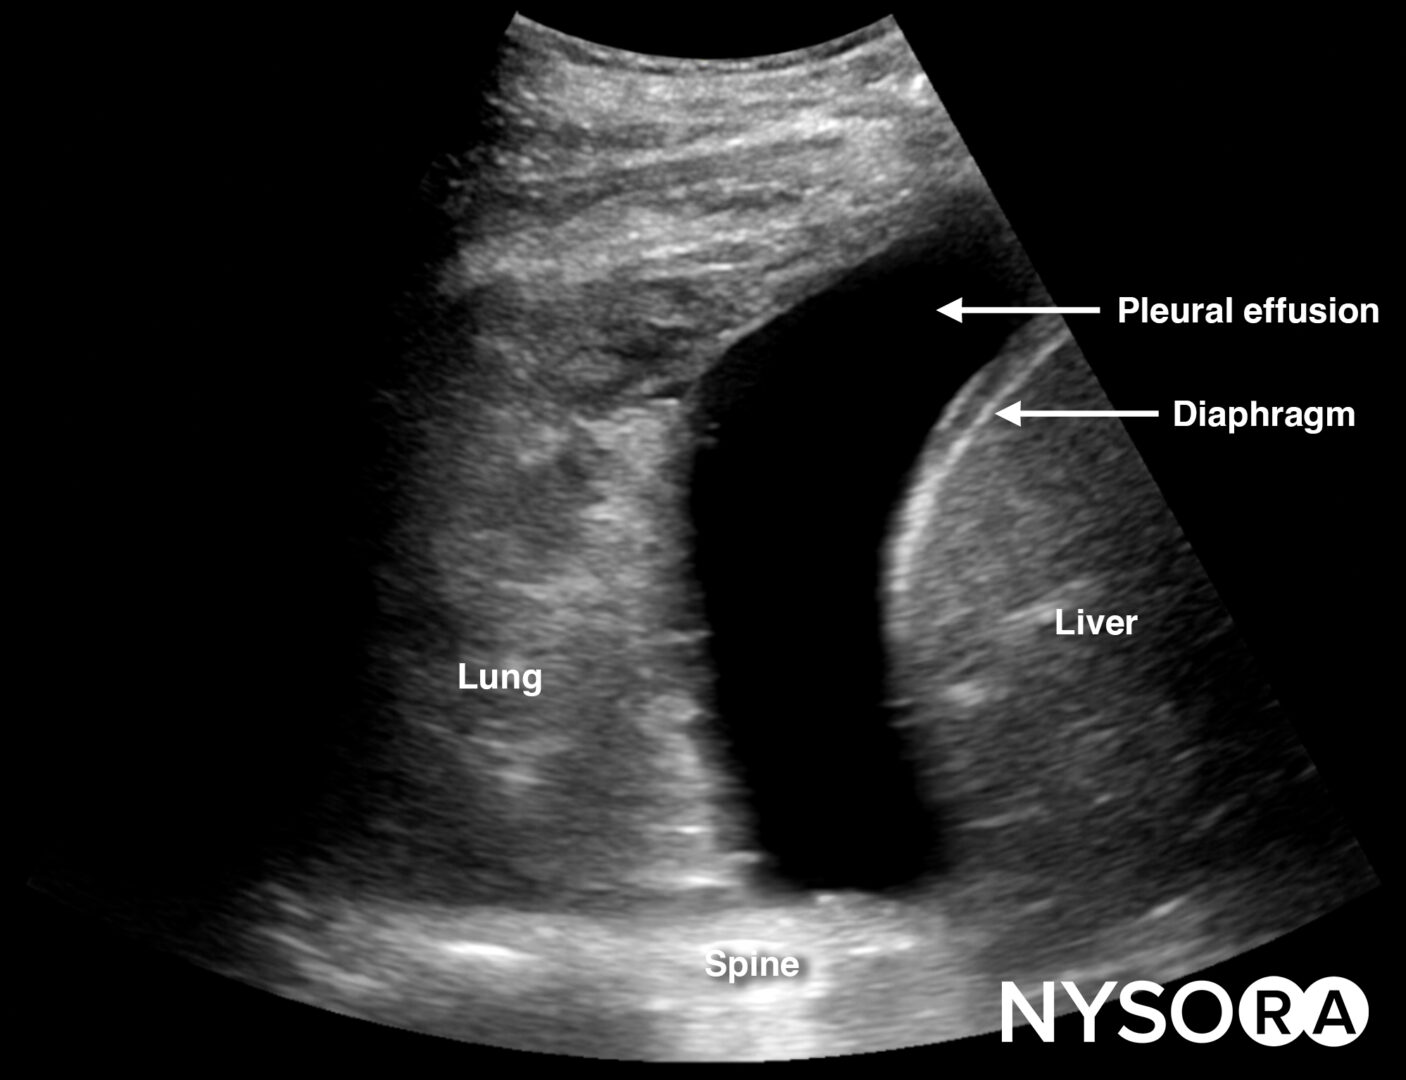

Free right intraperitoneal fluid collects between the liver and the kidney (Morrison’s pouch). If intrathoracic free fluid is present, it can be identified above the diaphragm.

Free intraperitoneal fluid is often found between the liver and the kidney, i.e., Morrison’s pouch.

Always assess the area above the diaphragm for free fluid in the RUQ and LUQ.

Free fluid or pleural effusion above the diaphragm.